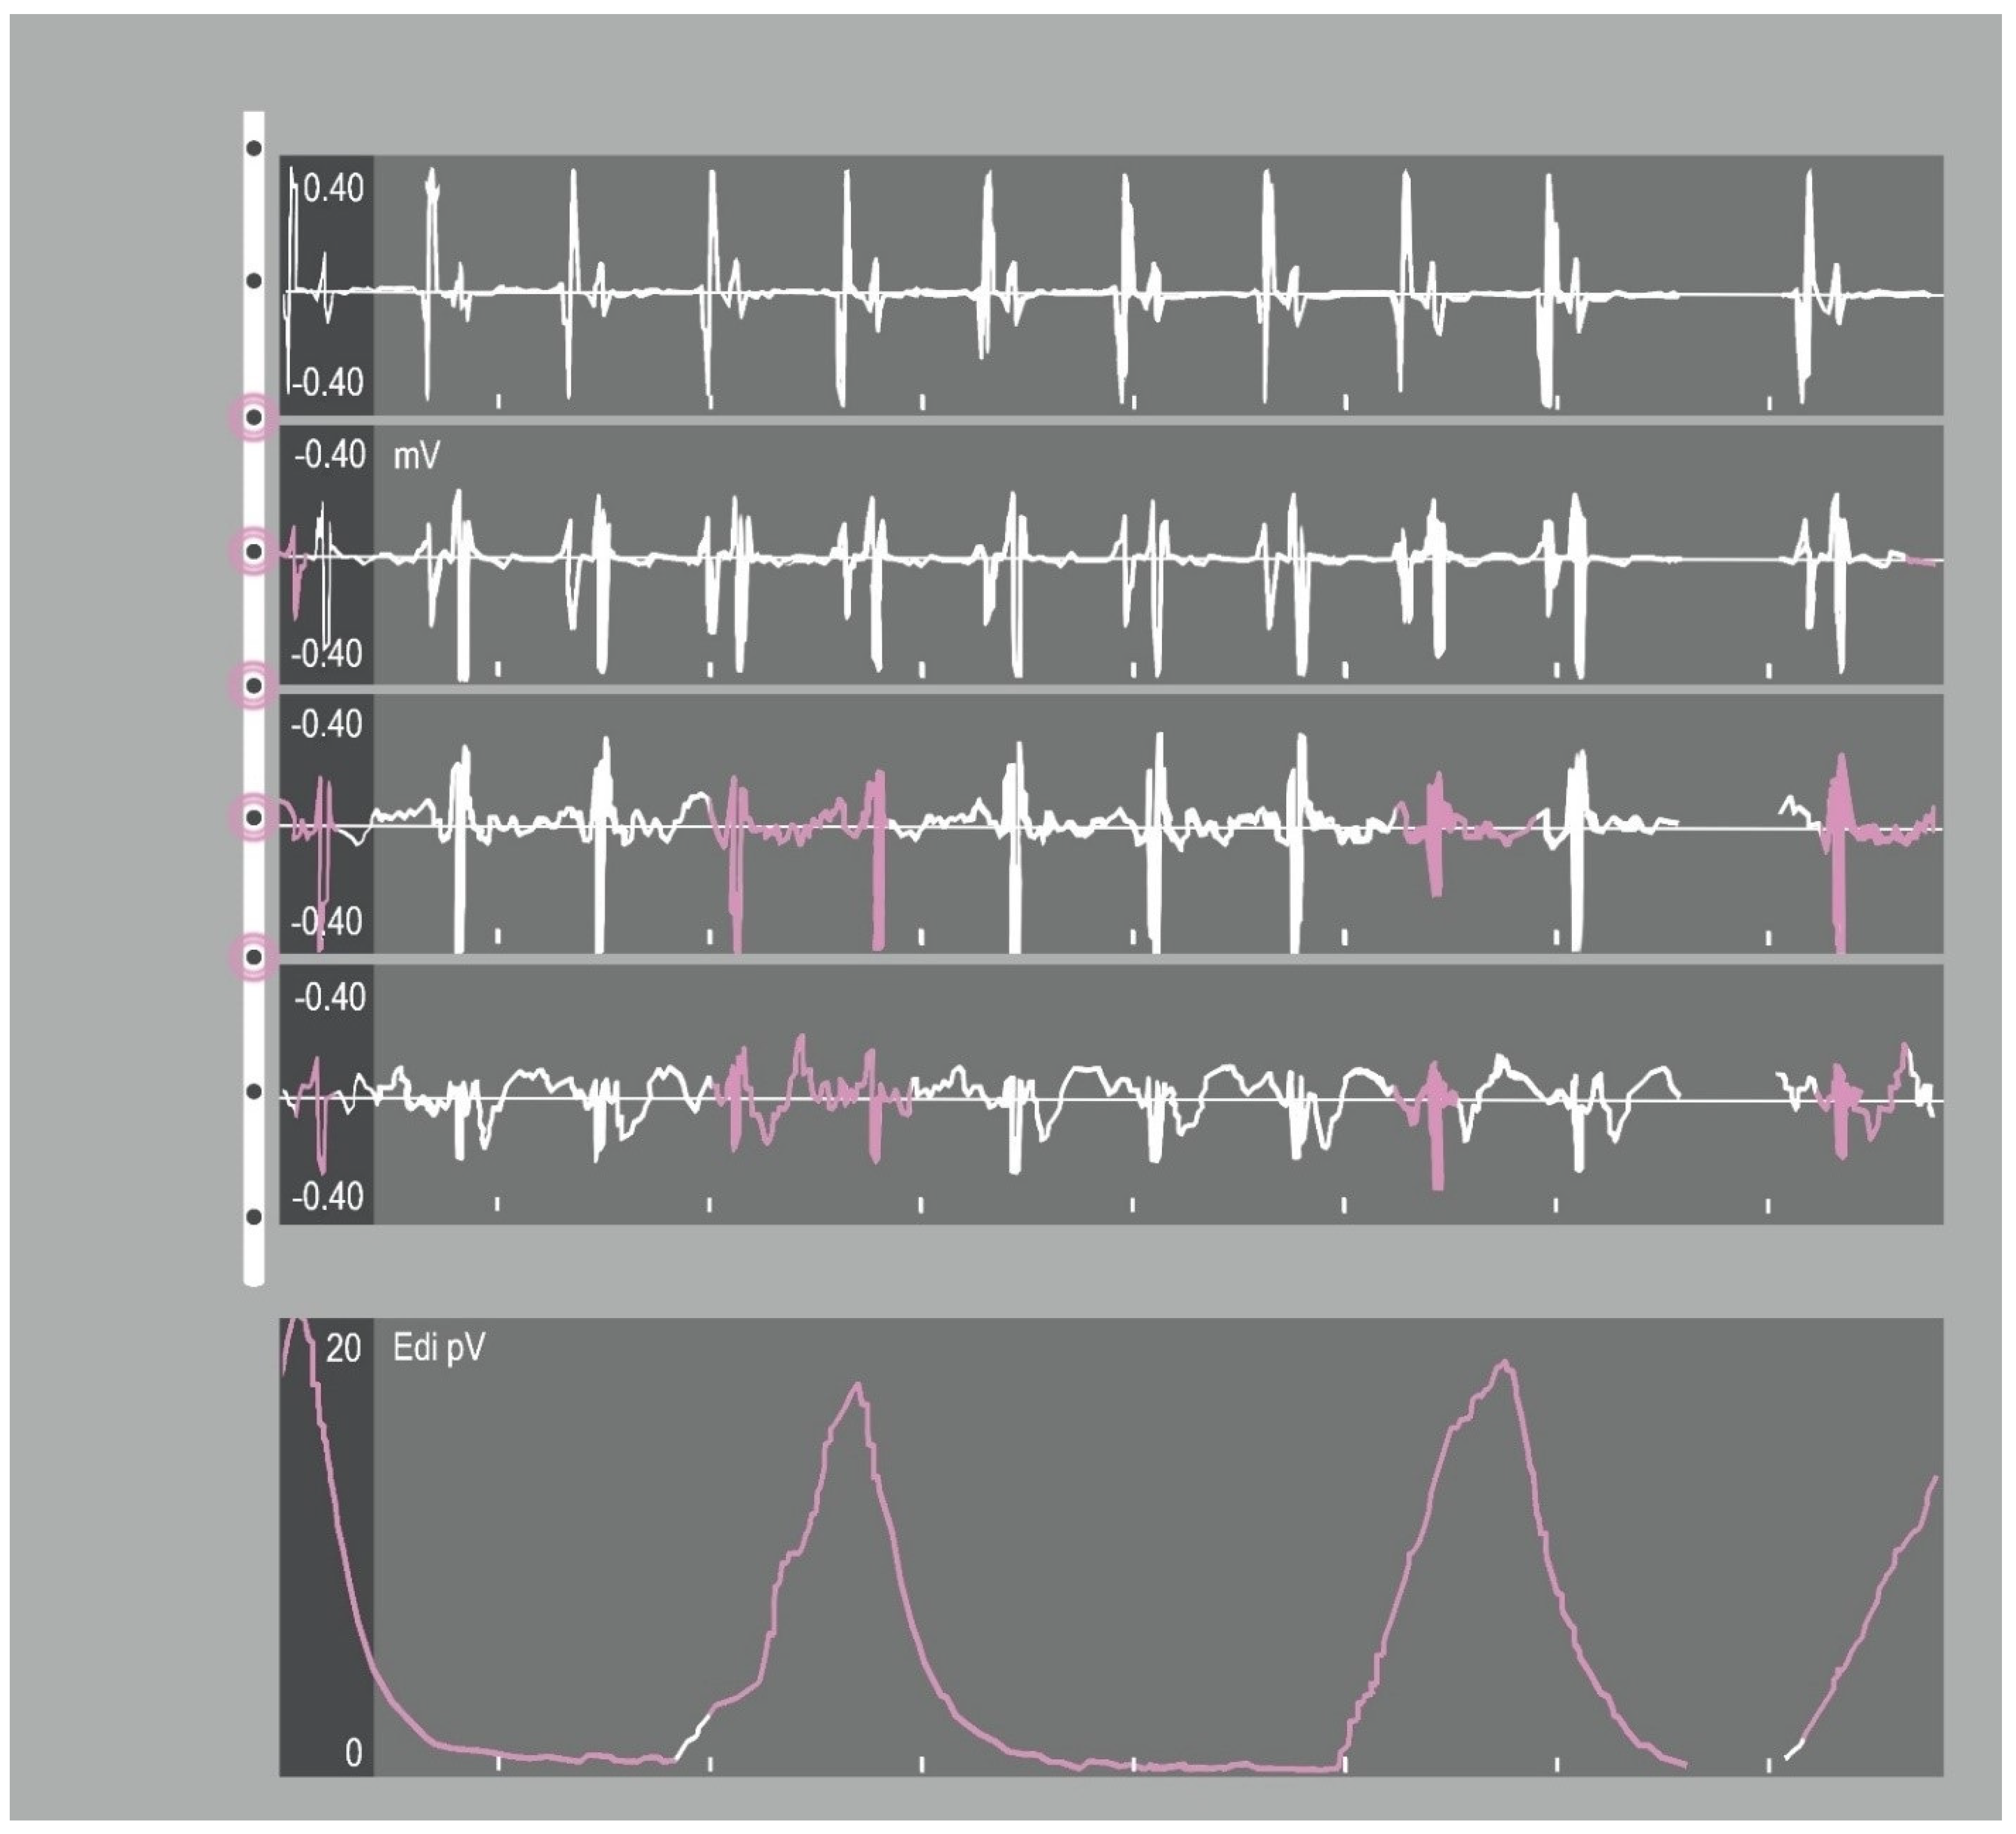

The timing and intensity of the EAdi signal determine the timing and intensity of the ventilatory assist, resulting in a high level of synchrony between the neural respiratory cycle and the flow of the ventilator, both in terms of time and flow assist. The pressure delivered by the ventilator is then directly proportional to both EAdi and NAVA level, and the airway pressure–time outline accurately reflects the EAdi profile (Figure 3).

Figure 3.

Representative tracings of airway pressure, flow, tidal volume and electrical activity of the diaphragm in a patient receiving NAVA. The figure shows how the pressure delivered by the ventilator is directly proportional to both EAdi and NAVA level, and the airway pressure-time outline accurately reflects the EAdi profile. Paw: Airway pressure; Vt: Tidal volume; EAdi: electrical activity of the diaphragm.